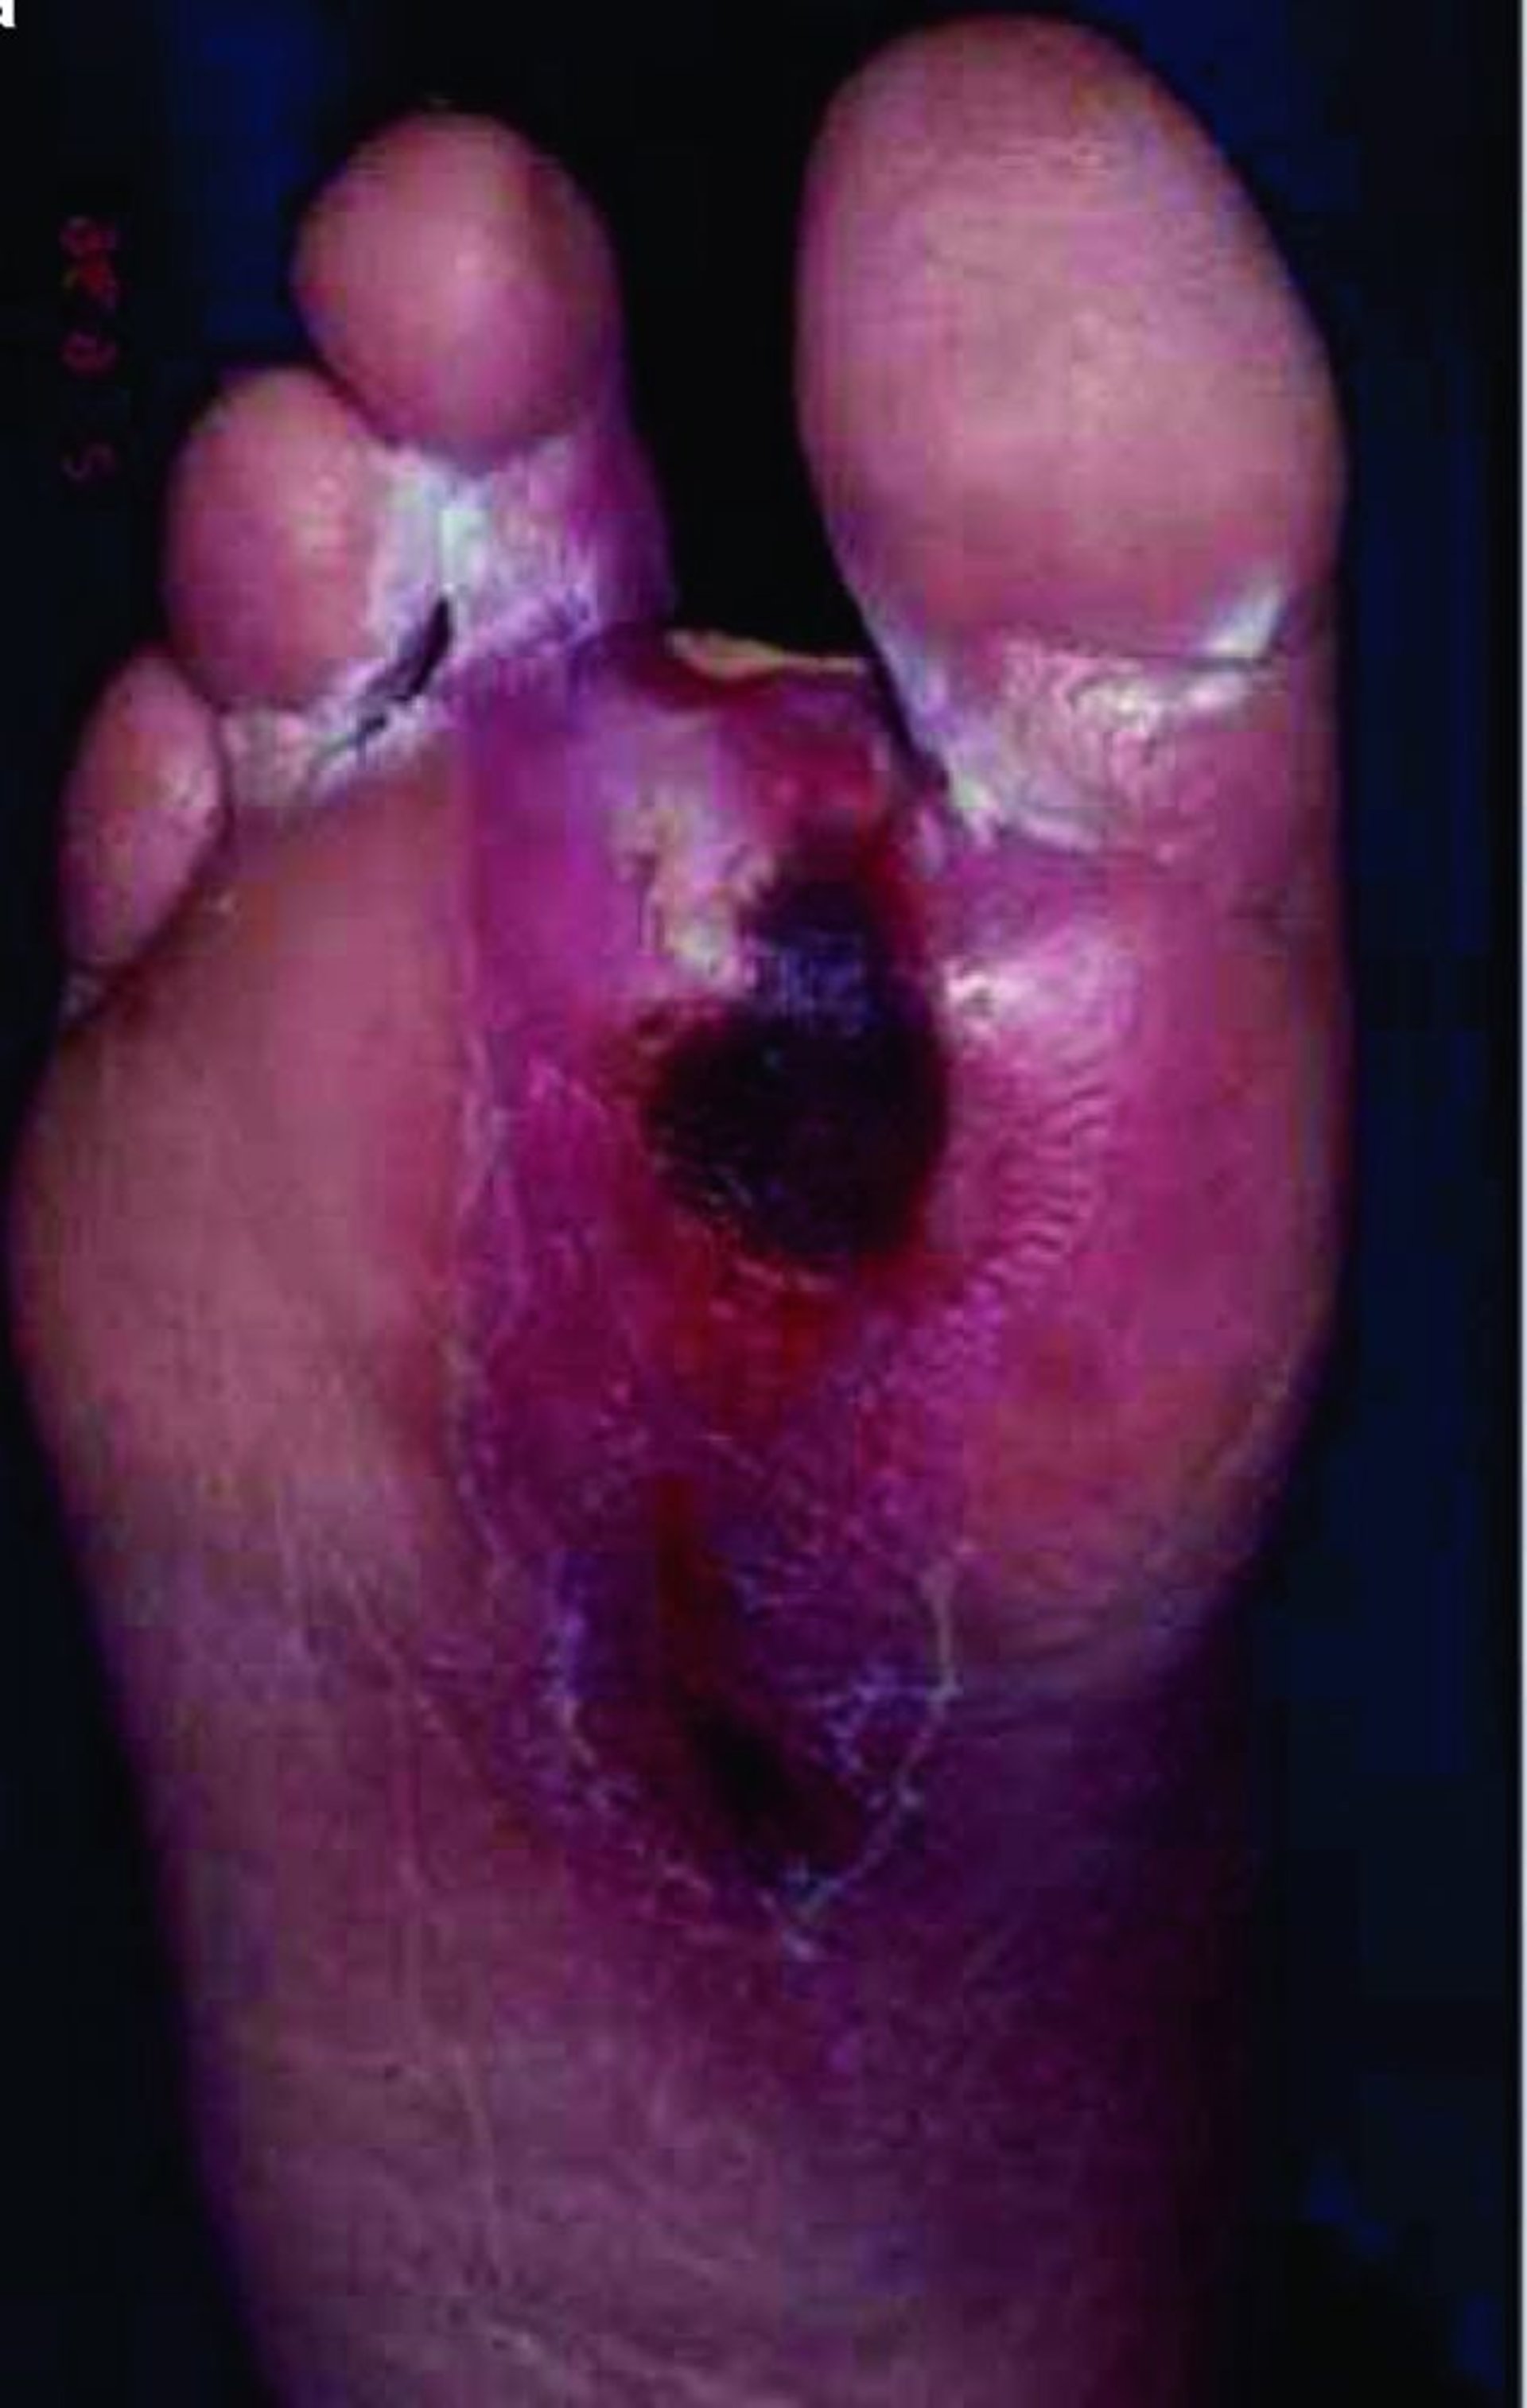

Ulcera del piede

Un paziente con diabete sviluppa spesso una microangiopatia, che può compromettere la cicatrizzazione cutanea, così che anche piccole lesioni della cute possono progredire in ulcere profonde e infettarsi facilmente, soprattutto negli arti inferiori.